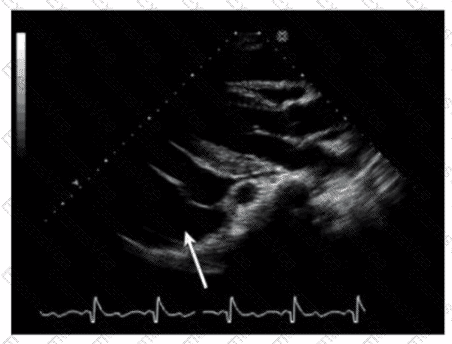

The echocardiographic image shows a structure posterior to the left atrium, pointed to by the arrow. This is consistent with a hiatal hernia, which often appears as an echolucent or mixed echogenicity structure behind the left atrium in the parasternal or apical views. Hiatal hernias occur when part of the stomach herniates through the esophageal hiatus of the diaphragm into the thoracic cavity and may mimic pericardial or pleural effusions on echocardiography.

Pericardial effusions appear as an anechoic (dark) space surrounding the heart but usually anterior or around the entire heart rather than posterior localized structure. Left pleural effusions also appear posteriorly but typically have different echogenicity and anatomical location. Ascites refers to free fluid in the abdomen and would not appear in this thoracic echocardiographic window.

Recognition of hiatal hernia on echocardiography is important to avoid misdiagnosis, as it may cause artifacts or false-positive effusions. The presence of swirling or movement of echogenic material with respiration and positional changes helps in diagnosis.